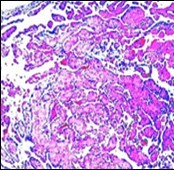

On microscopy, superficial squamous epithelial surface is intact. Sub-epithelial connective tissue stroma exhibits slit-like, vascular spaces. Upon extended magnification, multiple, intravascular papillary projections encompassed within a hyalinised stroma are discerned. Centroidal calcification appears in combination with intravascular, papillary endothelial cell proliferation, lined with singular layer of endothelial cells devoid of cytological atypia6, 7.

Characteristically, the vascular neoplasm denominates numerous papillae within blood vessels. Papillae are coated with singular or dual layer of flattened endothelial cells with an encompassing hyalinised, fibrous tissue core. Vascular lumen is distended with thrombosis. Foci of haemorrhage with fibrinous and purulent exudate are discerned. Tumour perimeter depicts inflammatory granulation tissue. Cholesterol clefts and focal reactive bone formation may concur. Extraneous squamous epithelium may be discontinuous and ulcerated. The neoplasm is devoid of features of malignancy4, 6.

Numerous micro-calcifications can be observed within the lesion which may engender vascular occlusion and tissue necrosis6. Figure 1, Figure 2, Figure 3, Figure 4, Figure 5, Figure 6, Figure 7, Figure 8.

Figure 4.Papillary endothelial hyperplasia enunciating papillary arrangements coated with single layer of endothelial cells intermingled with significant fibrinous and thrombotic exudate13.